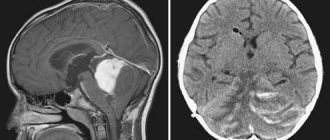

Prices Make an appointment One of the most important structures of the brain is the cerebellum. It is located